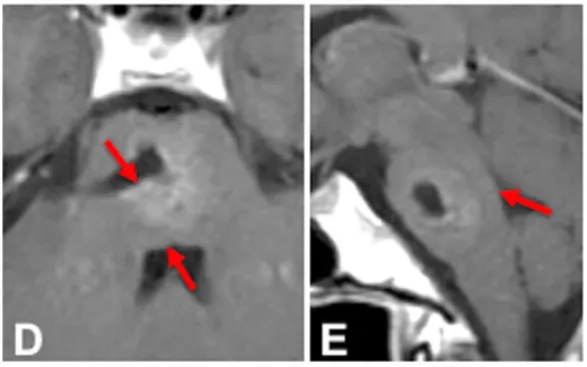

脑桥中部横断面图像标示下方脑桥海绵状血管畸形(PCM)。该血管性病变未紧贴脑桥表面,但单侧推移周围内在结构,包括外展神经与面神经的神经核团及纤维束。解剖学研究显示,面神经核距第四脑室底平均约5.1毫米,外展神经核距菱形窝表面平均仅0.2毫米。绿色箭头指示抵达左侧病变的两种可能手术入路:后内侧入路或后外侧入路。p-laterally=后外侧;后内侧。